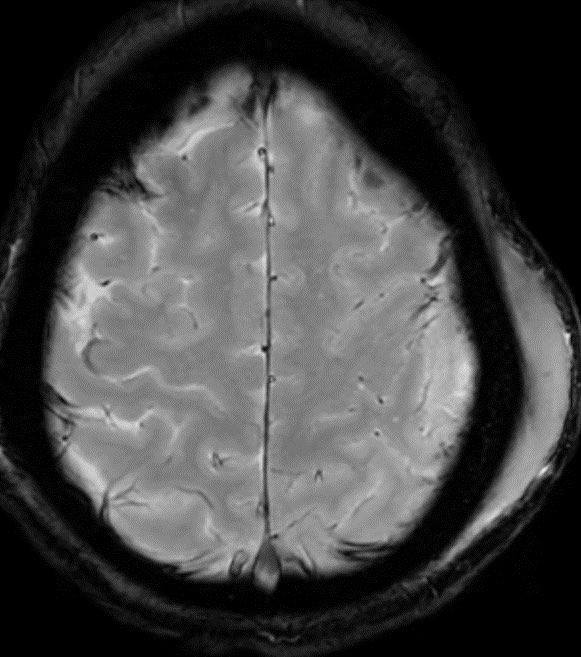

⭐️ Answer: Cortical vein thrombosis (CVT)